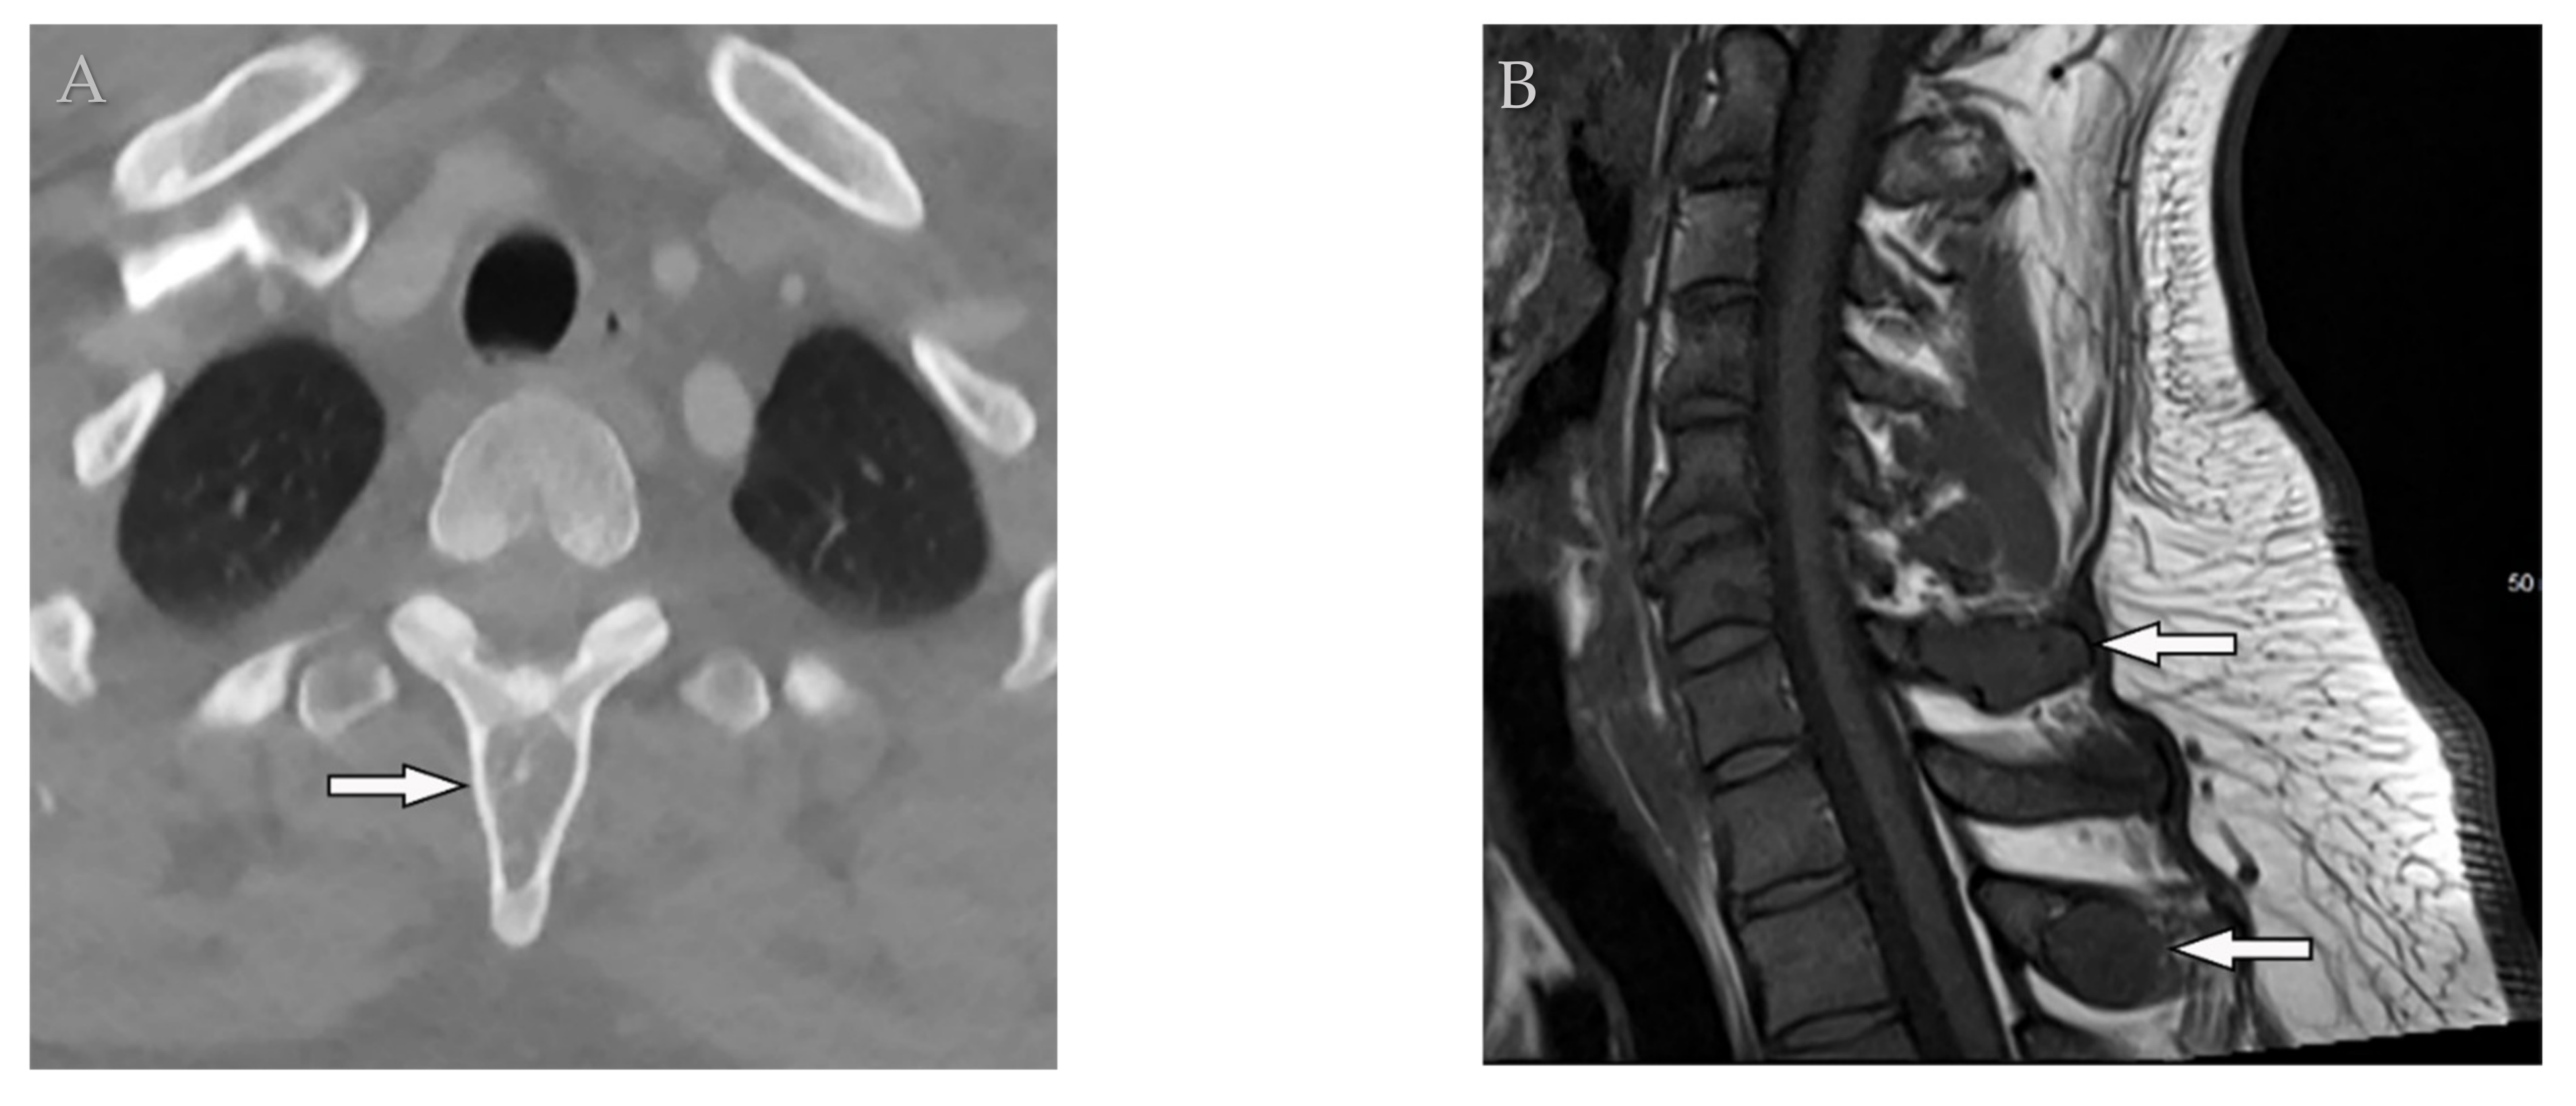

8.1. Pyogenic Spondylodiskitis

8.2. Tuberculosis Spondylodiskitis

- Hong, S.H.; Choi, J.-Y.; Lee, J.W.; Kim, N.R.; Choi, J.-A.; Kang, H.S. MR Imaging Assessment of the Spine: Infection or an Imitation? Radiographics 2009, 29, 599–612. [Google Scholar] [CrossRef]

- Ramadani, N.; Dedushi, K.; Kabashi, S.; Mucaj, S. Radiologic Diagnosis of Spondylodiscitis, Role of Magnetic Resonance. Acta Inf. Med. 2017, 25, 54–57. [Google Scholar] [CrossRef]

- Kumar, Y.; Gupta, N.; Chhabra, A.; Fukuda, T.; Soni, N.; Hayashi, D. Magnetic resonance imaging of bacterial and tuberculous spondylodiscitis with associated complications and non-infectious spinal pathology mimicking infections: A pictorial review. BMC Musculoskelet. Disord. 2017, 18, 244. [Google Scholar] [CrossRef]

- Yeom, J.A.; Lee, I.S.; Suh, H.B.; Song, Y.S.; Song, J.W. Magnetic Resonance Imaging Findings of Early Spondylodiscitis: Interpretive Challenges and Atypical Findings. Korean J. Radiol. 2016, 17, 565–580. [Google Scholar] [CrossRef]